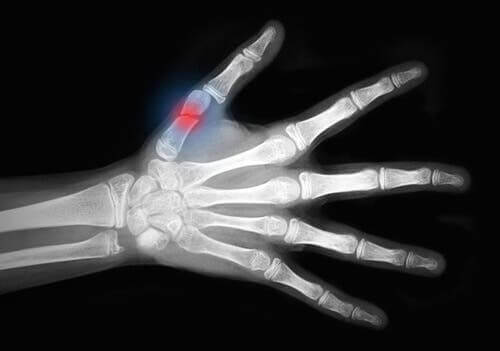

Tıbbi alanda, soyulma yaralanmaları, derideki yumuşak dokunun geniş bölümünün soyulduğu ve kemiğin göründüğü travmatik yaralanmalardır.

Son olarak, III. derece yaralanmaları. Bu yaralanmalar, aşağıdaki örneklerde olduğu gibi ciddi deri ve kas hasarları ile ilişkilidir.

- Soyulma yaralanmaları

Gördüğünüz gibi, soyulma yaralanmaları yumuşak doku yaralanmalarının en ciddi grubunda yer almaktadır.